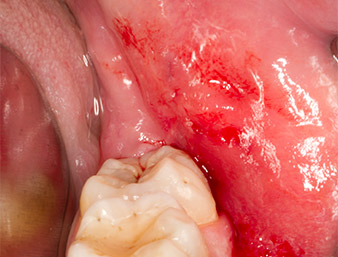

After block and local anaesthesia, the operating site was opened up and the soft tissue exposed for buccal retromolar access (Fig. 3).

The tissue above the root remnant was not completely ossified and consisted for the most part of granulation tissue modified by inflammation (Fig. 4).